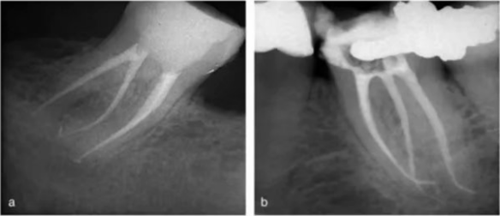

大部分 C 型根管系統(tǒng)在根管口處為連續(xù)的 C 型結(jié)構(gòu);但是,沿著牙齒牙根方向,橫截面形狀可能是 C1,C2 或 C3 的任一種。C4 和 C5 幾乎只能在根尖附近的橫截面見到(圖 15a-c)。C 型根管的下頜磨牙在清理、預(yù)備成型及充填方面都存在挑戰(zhàn),特別是,當(dāng)髓室底發(fā)現(xiàn)C 型根管口時(shí),不能確定根管在到達(dá)牙根根尖 1/3 時(shí)是否是連續(xù)的。在定位 C 型根管系統(tǒng)主根管分叉為兩根管或三根管的部位及識(shí)別根管間的峽部時(shí),手術(shù)顯微鏡是很有幫助的(圖16a-b)。C 型根管沖洗時(shí)應(yīng)盡量使用超聲銼活化沖洗液。

事實(shí)上,在根管充填前進(jìn)行 1 分鐘的超聲蕩洗可以增加根管及峽部的清潔程度。應(yīng)使用熱牙膠垂直加壓技術(shù)充填C 型根管,特別是在這些困難的錯(cuò)綜復(fù)雜的根管系統(tǒng)中,也能完成三維的根管充填(圖 17a、b)。